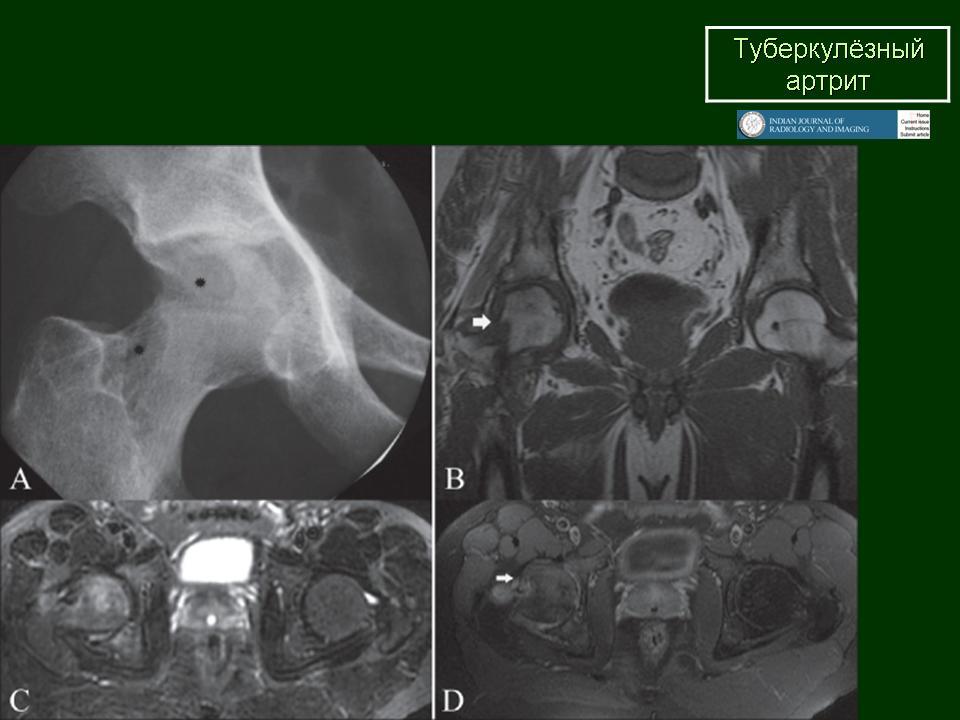

Туберкулез тазобедренного сустава (коксит)

Поражения тазобедренного сустава также относятся к одной из частых локализаций костно-суставного туберкулеза и на его долю приходится около 20% случаев поражений костей при туберкулезе.

Если раньше считалось, что почти 60% случаев приходится на детей первого десятилетия жизни, то в настоящее время туберкулез тазобедренного сустава стал относительно часто встречаться у лиц старшего возраста.

Ранние клинические проявления специфического поражения тазобедренного сустава незначительны. Это хромота, которая сначала возникает периодически, а затем, через 2—3 месяца,

становится постоянной. Боли носят непостоянный характер. Постепенно появляется ограничение движений и у детей возможно удлинение конечности.

При рентгенологическом исследовании в преартритической фазе самым ранним симптомом является остеопороз, который может быть незначительным и выявляться лишь на сравнительных рентгенограммах с захватом двух тазобедренных суставов. Еще до появления туберкулезного остита могут отмечаться изменения со стороны мягких тканей в виде увеличения теней межмышечных прослоек между контурами суставной сумки и малой и средней ягодичными мышцами (симптом Ланге — Будинова). Отмечается также асимметрия костей малого таза (симптом Пинхасика), обусловленная неправильным положением больного из-за атрофии мышц, или наоборот утолщением сустава на больной стороне, или вследствие болевой контрактуры. Зная наиболее частую локализацию туберкулезных оститов вокруг тазобедренного сустава можно выявить участки нарушения костной структуры, нечеткость костных трабекул. Спустя 1,5—2 месяца выявляются очаги деструкции костной ткани с нечеткими неровными контурами, которые могут содержать множественные губчатые секвестры. Наиболее часто туберкулезные оститы располагаются в костях, образующих вертлужную впадину, реже они встречаются в шейке, и как исключение в головке бедренной кости. Причем очаги деструкции костной ткани, расположенные в вертлужной впадине, лучше выявляются на задних рентгенограммах, а очаги деструкции в шейке бедра, особенно в нижне-внутреннем отделе ее лучше выявляется на рентгенограммах с отведением бедра (по Лауенштейну). У некоторых больных наблюдается ранняя деформация ядра окостенения головки бедра в виде его увеличения.

При переходе процесса на сустав клинические симптомы становятся постоянными и выраженными. К болям присоединяется сгибательная контрактура, усиливается атрофия мышц бедра. Натечные абсцессы могут выявляться в передне-наружном отделе бедра, реже в области ягодичных мышц.

Артритическая фаза (при переходе процесса на сустав) на рентгенограммах характеризуется усилением остеопороза, который постепенно распространяется на все кости нижней конечности. Суставная щель асимметрично суживается, больше в верхне-наружных отделах. В дальнейшем сужение суставной щели достигает значительной степени. Суставные поверхности костей теряют свои очертания, их контуры становятся нечеткими, неровными. Выявляются краевые, без четких контуров содержащие секвестры, очаги деструкции костной ткани. Последние могут вызывать значительные разрушения вертлужной впадины, головки и даже шейки бедренной кости, смещение головки бедра вверх.